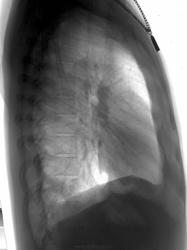

Молодая барышня 28 лет. На момент проведения ц ФГ жалоб нет. Представлена для контроль аналоговая рентгенограмма двухнедельной давности. Динамика отсутствует (посему не выставляю)

В тот же день проведена КТ (о результате информирован лечащим врачом). Ваше мнение?

Шаровидная тень: в S4 в/доли слева (1 случай) и S10 н/доли справа (2 случай)

Татьяна Валентиновна, асолютно согласен. что основной рентгенологический признак - шаровидные тенеобразования, но...достаточно ли они "шаровидны" и достаточно ли однородны....+молодой, в общем то возраст, + отсутствие существенных жалоб. Конечно, смущает тот факт, что это не первые их ФГ (но у меня то они впервыеwink). Опять же - в С10 (скрывается за тенью печени), в С4 слева (не факт, что раньше было перекрыто левым краем сердца) и, как следствие - не были обнаружены.

Внутрилегочная секвестрация или артериовенозная мальформация.

..... артериовенозная мальформация.

Она самая))). Да, оба случая подтверждены на КТ.